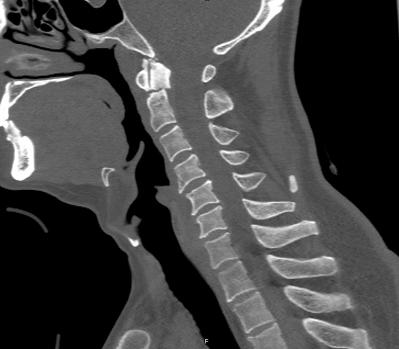

近日,45岁的王先生因高处坠落伤致颈部疼痛、活动受限,于是到北京友谊医院就诊。结合CT结果,医生诊断王先生为枢椎齿状突II型骨折,需手术治疗,王先生被收入骨科病房。

辅助检查显示:颈椎前部可及多发血肿,枢椎齿状突骨折部位向后方移位。

骨科主任医师唐海、单建林两位专家分析患者病情认为,王先生为枢椎齿状突的血运呈双侧雨刷状分布,保守治疗骨折不愈合的风险极大。行内固定手术无疑是最佳的选择,但是手术部位高位颈髓是生命中枢,手术难度极大,对术者的操作要求较高,如有不慎,会给患者带来灾难性后果。经过仔细地考虑,唐海与单建林为患者制定了详细的手术计划,决定实施枢椎齿状突骨折内固定手术。